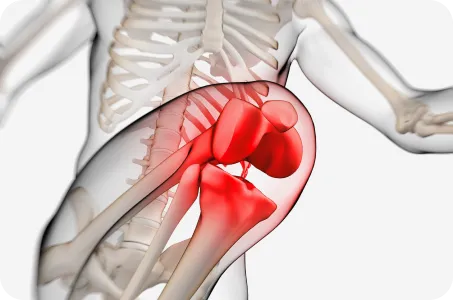

고관절 , 대퇴골, 경골, 거골, 중족골 중 어느 부위의 문제인지 정확히 파악하는 것이 중요합니다.

안짱다리 유형

대퇴골 내회전

허벅지 뼈가 안쪽으로 틀어진 경우

경골 내회전

종아리 뼈가 안쪽으로 틀어진 경우

중족골 내전

발이 안쪽으로 휘어 있는 경우